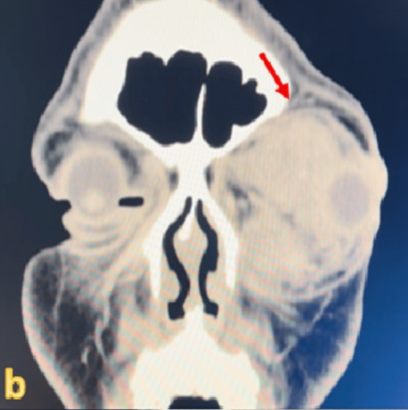

CT 촬영 결과, 시신경을 심하게 누르고 있는 큰 종양이 발견됐다. 이후 제거 수술을 받았으나, 이미 손상된 시신경은 회복되지 않았다.

두 번째 사례 환자는 42세 여성이다. 최근 3개월간 오른쪽 눈이 붓고, 사물이 두 겹으로 보이는 증상이 나타났다.마찬가지로 CT 검사에서 종양이 확인됐고, 즉시 제거 수술을 받았다.